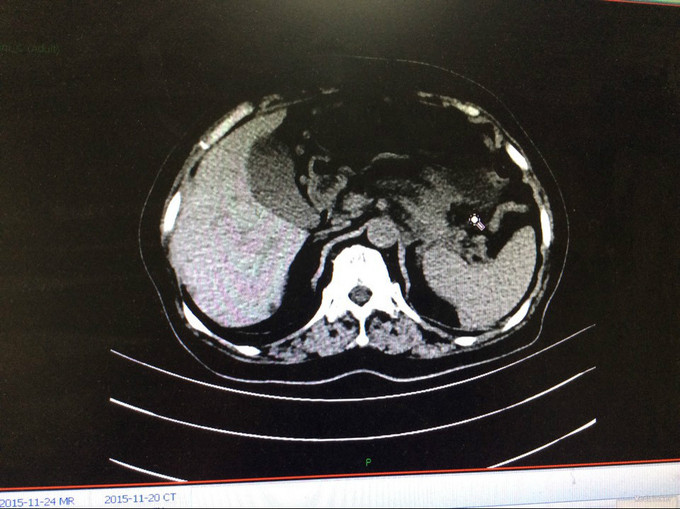

查体:生命体征平稳。神智清,查体合作,面容正常,淋巴结未触及肿大。双肺听诊呈清音,为闻及干湿罗音及哮鸣音;心率78次/分,律齐,无异常心音及心脏杂音;腹平软,肝脾肋下未及,未触及肿块,无压痛及反跳痛,肠鸣音正常。双下肢无水肿,生理反射存在,病理反射未引出。专科查体:无明显异常。辅助检查:湖北省中医院CT示:胰腺占位。CT检查示:1.结合原CT、MR检查,胰腺体尾部及周围异常改变,考虑胰腺炎伴坏死囊性变可能性大,与2015-11-20CT相比较,囊性病变略缩小;腹膜后淋巴结增多增大,大致同前;2. 所及肝脏多发囊肿;肝右叶后段其中一个病变边缘可疑强化,大小与前次相仿;3. 左侧肾上腺饱满。 MRI检查示: 胰腺体尾部及周围异常改变,考虑胰腺炎伴坏死囊性变可能性大,合并肿瘤性病变待排,病变累及腹膜伴腹膜后淋巴结增多增大,腹腔少许积液,请结合检查结果考虑;2. 所及肝脏多发囊肿;肝右叶后段其中一个病变边缘可疑强化,需鉴别于血管瘤与转移性病变,建议随访复查;3. 左侧肾上腺饱满;4. 所及右侧胸廓外小结节(层面16-7),直径约4mm,不除外右乳的病变:5. 所及腰椎骨性纵裂畸形。病理检查:(胰体尾部肿块穿刺组织)高分化腺癌,考虑为IPMN相关性浸润性癌。